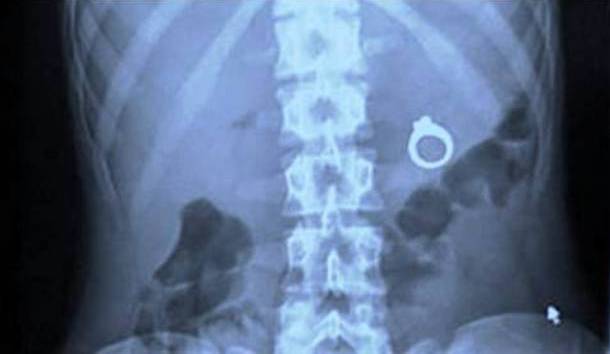

Weirdest Things Found On An X-Ray

1. X-Ray of a Suicide Bomber

*All images sourced from Reddit*This is a hand grenade inside a stomach of someone who was a suicide bomber. He had planned to trigger the bomb as a part of an attack - but, the plan thankfully did not work as once the bomb was inside his stomach he had no way of triggering it...Advertisement